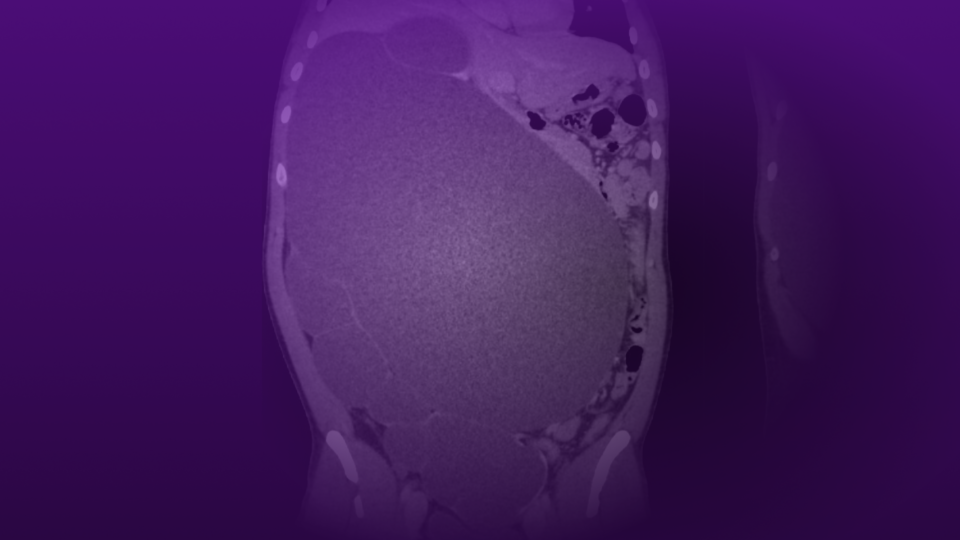

After successfully adopting a vegan diet for several months, the patient was able to discontinue medication for erections and urinary symptoms. In addition, at the most recent follow-up, he had lost 11 pounds and his blood pressure had improved (Figure 1).